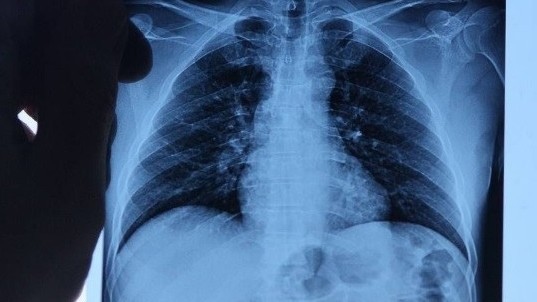

Echinococcosis incidence rate grows 1.3 times in Kyrgyzstan

AKIPRESS.COM - The number of echinococcosis cases has grown by 1...